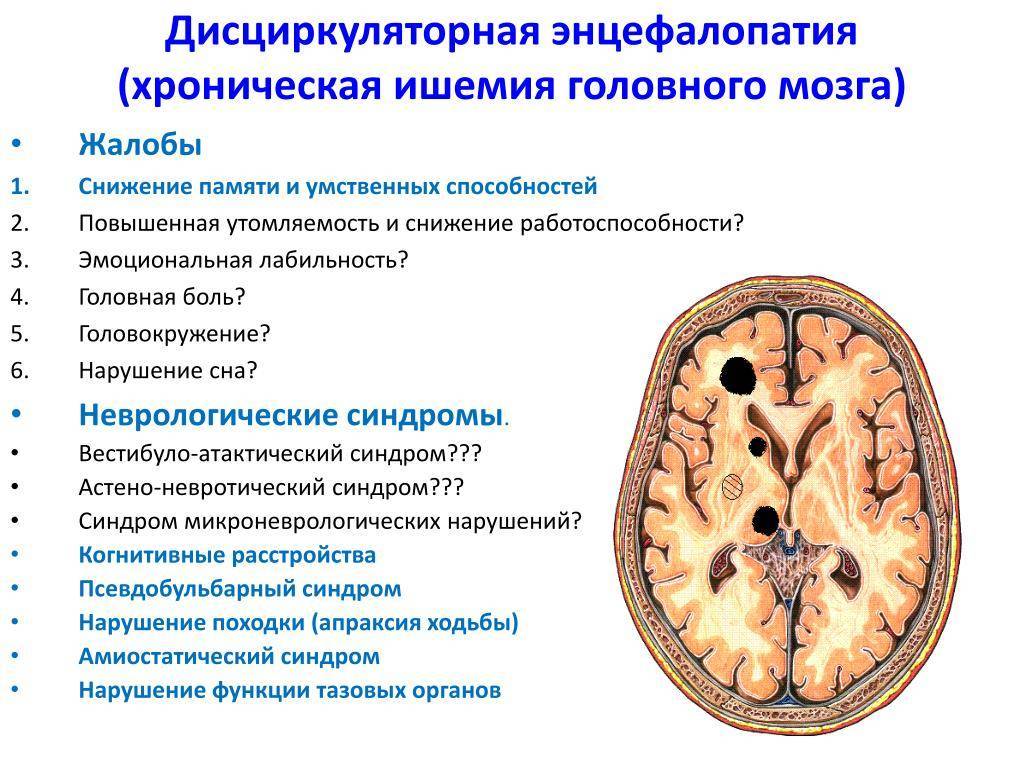

Особенности и диагностика левостороннего кровотока